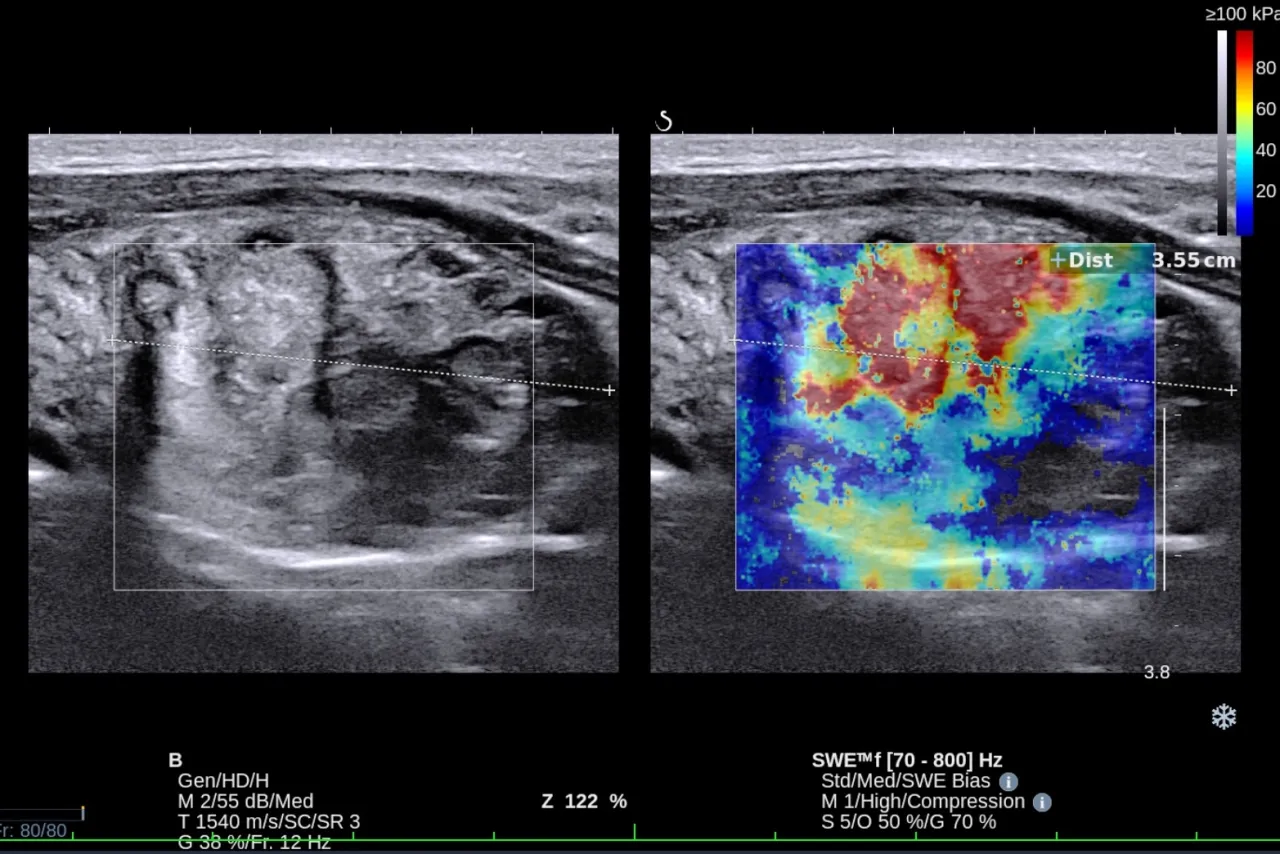

USG tarczycy zaglądamy do środka krok po kroku

Kiedy badania krwi sygnalizują problemy z tarczycą lub lekarz chce ocenić jej strukturę, kolejnym krokiem jest zazwyczaj badanie ultrasonograficzne.

Dlaczego USG jest kluczowym badaniem obrazowym tarczycy?

USG tarczycy to podstawowe, nieinwazyjne, bezbolesne i bezpieczne badanie obrazowe, które dostarcza niezwykle cennych informacji o stanie Twojej tarczycy. Dzięki niemu lekarz może dokładnie ocenić jej:

- Wielkość i kształt: Czy tarczyca jest powiększona (wole) lub zmniejszona?

- Strukturę miąższu: Czy jest jednorodny, czy występują zmiany zapalne, typowe np. dla choroby Hashimoto (tzw. obniżona echogeniczność)?

- Obecność zmian ogniskowych: Takich jak guzki, torbiele czy zwapnienia. USG pozwala precyzyjnie zlokalizować te zmiany, ocenić ich rozmiar, kształt, granice i unaczynienie, co jest kluczowe w różnicowaniu zmian łagodnych od potencjalnie złośliwych.

Jest to badanie niezastąpione w diagnostyce wola guzkowego oraz w monitorowaniu przebiegu chorób autoimmunologicznych tarczycy.

Co lekarz widzi na monitorze? Ocena wielkości, guzków i stanu zapalnego

Podczas badania USG lekarz zwraca uwagę na szereg szczegółów, które pomagają w postawieniu diagnozy:

- Wielkość i kształt tarczycy: Czy mieści się w normie, czy jest powiększona (wole).

- Echogeniczność miąższu: Czy tkanka tarczycy jest jednorodna, czy występują obszary o zmienionej echogeniczności, co może świadczyć o stanie zapalnym (np. w Hashimoto).

- Obecność guzków: Jeśli guzki są obecne, lekarz ocenia ich rozmiar, kształt, granice (czy są regularne, czy nieregularne), unaczynienie (czy są dobrze ukrwione), oraz obecność mikrozwapnień, które mogą być cechą niepokojącą.

- Węzły chłonne: Ocenia również okoliczne węzły chłonne, szukając ewentualnych powiększeń.